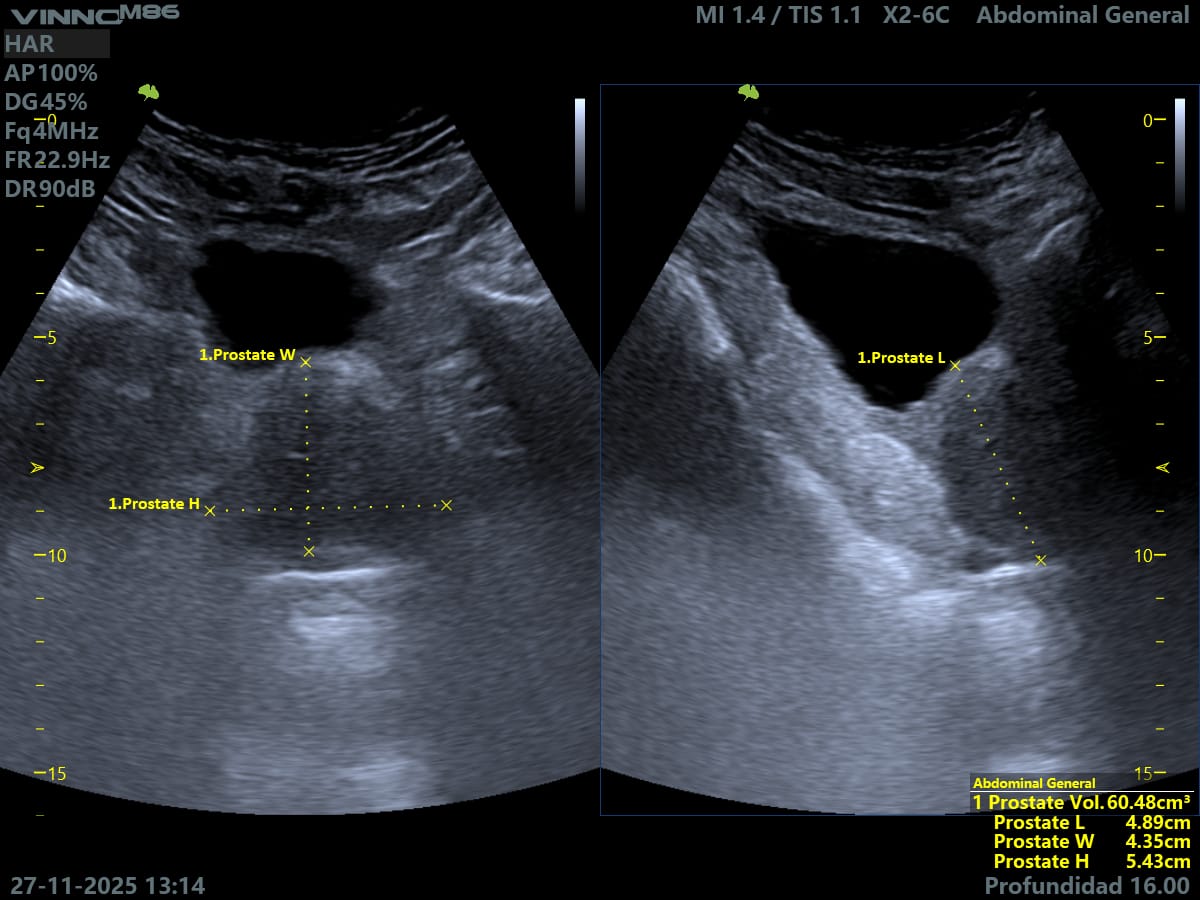

Ecografía: hipertrofia benigna de próstata con volumen de 60,48 cm cúbicos y divertículo vesical de 3,98 x 2,58 cm.